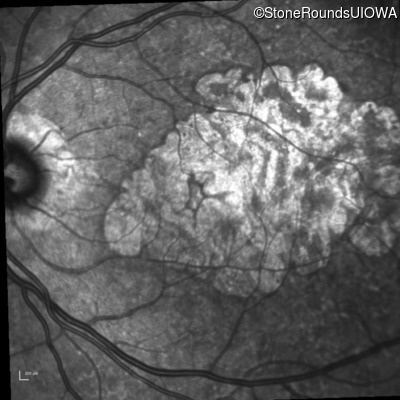

Infrared Fundus Photograph - Right - 20/25

Exemplar

Infrared Fundus Photograph - Left - 20/25 -2